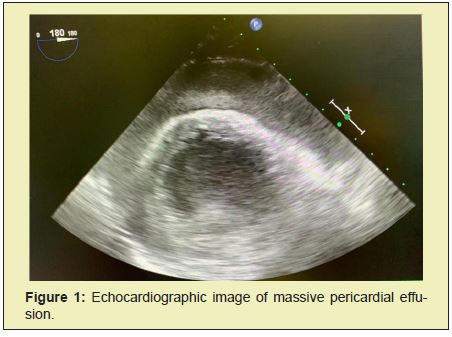

ST segment elevation and Q Waves in the anterior leads are evident on the electrocardiogram (EKG). Transthoracic echocardiography (TTE) revealed a severe depression of the left ventricular systolic function, an apical aneurysm with a distal rupture of the posterior ventricular wall and a massive pericardial effusion compromising right ventricular filling (Figure 1). Vasopressor support was initiated. The case was then discussed with the cardiothoracic surgeons and the anaesthetic team of the central hospital of reference who decided to admit the patient for an emergent pericardiotomy. Immediately upon arrival at the operating room, standard preoperative monitoring was applied along with near-infrared spectroscopy (NIRS). The induction was performed with iv propofol 30 mg, fentanyl 50 mcg and rocuronium 50 mg. Once the incision was made, blood and a giant clot were seen within the pericardial space (supplemental video 1). There was sudden hemodynamic recovery following clot removal with a pronounced improvement of arterial pressure. Furthermore, the baseline non-invasive cerebral oxygen saturation (SctO2) levels of 45% and 40% for the left and right sides of the brain respectively, immediately increased at this time to around 75% bilaterally (Figure 2), showing rapid recovery of cerebral perfusion pressure and therefore resolving the superior vena cava syndrome secondary to the cardiac tamponade.